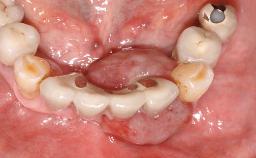

Oral implants are highly successful and offer long-term benefits, especially in the rehabilitation of edentulous patients or patients with oral defects following ablative tumor surgery (Albrektsson and coworkers 1986), and also after radiation therapy (Schiegnitz and coworkers 2014). With the number of implants placed globally going into the millions, implant dentists have observed some rare adverse events. Although carcinogenesis around implants is an exceedingly rare phenomenon, we recently reported about 15 patients treated for carcinomas adjacent to implants at our clinical department over a period of fifteen years (Moergel and coworkers 2014). The following case represents a patient of this cohort; it discusses possible risk factors and makes suggestions for a recall schedule. A 70-year-old woman was referred to our outpatient department for evaluation of a rapidly growing macroscopic alteration of the mucosa in the left mandible.

| Jaw | Mandible |

| Area | Posterior |

| # of Teeth | 7 |

| # of Implants | 4 |